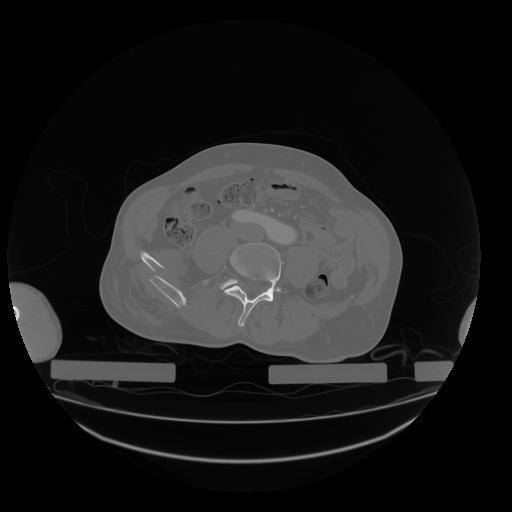

28 CUERPO,CE,Vol,2.0,CUERPO,,